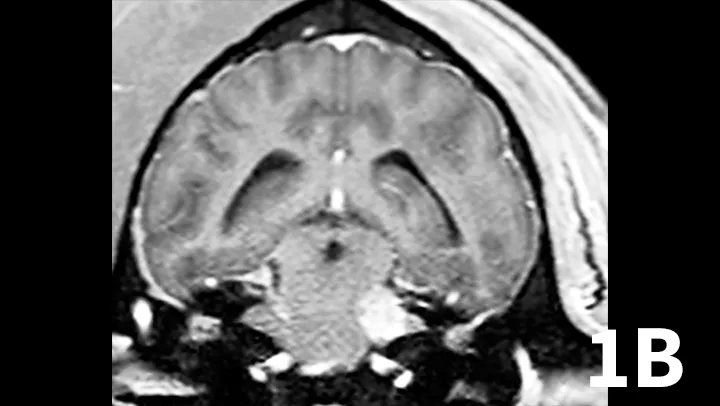

Animals may have erythema and pruritus affecting the external ear or pinna, odor or discharge from the ear, and pain in addition to signs of peripheral vestibular disease. Although diagnosis can be suggested by otoscopy, advanced imaging is superior, as it permits visualization of the osseous bulla and inner ear. The author typically prefers MRI to image dogs suspected of otitis interna because it is superior to computed tomography (CT) for detecting intracranial extension of lesions and detecting other causes masquerading as otitis interna. On MRI, bullae may appear thickened and are usually filled with T2-hyperintense/T1–iso-hypointense (dark) material; abnormal tissue within the bulla usually contrast-enhances T1WI (Figure 2). On T2WI, there may be a loss of signal within the inner ear. Myringotomy and deep ear flush are recommended to identify the underlying infectious agent and assist in removing debris or pus that will prohibit clearance of infection. Antimicrobial therapy is typically continued for 6 to 8 weeks, as bone infection is likely.

Transverse T2WI (A) and T1WI (B) from a 6-year-old cocker spaniel with a 6-month history of left peripheral vestibular disease that acutely worsened, with signs consistent with central localization. The left middle ear cavity is filled with T2-hyperintense material (arrowhead). The left inner ear is hypointense (arrow) compared with the right side. In addition, the left medulla and cerebellum contains patchy T2-hyperintense lesions. T1 postcontrast images show enhancement of the meninges (arrowhead) and a mass-like, enhancing lesion adjacent to the internal acoustic meatus. These findings are consistent with chronic otitis interna and media with secondary extension into the meninges and central nervous system.